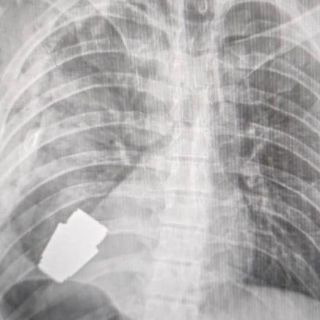

¡Increíble! Extraen granada del pecho a un soldado ucraniano sin que explotara

Los cirujanos llevaron a cabo una delicada operación neutralizando el explosivo que estaba alojado justo debajo del corazón del soldado

El gobierno ucraniano describió como un "susto afortunado" la terrible experiencia por la que tuvo que pasar un soldado herido, a quien le extrajeron con éxito una granada que se encontraba en su pecho.

Agregó que la granada fue extraída bajo la supervisión de dos militares expertos en explosivos para tratar de asegurar la seguridad de los médicos y dar indicaciones para evitar que fuera detonada.

Maliar contó que la operación estuvo a cargo del cirujano militar, Andriy Verba, de 57 años, considerado uno de los más experimentados doctores del ejército ucraniano.

Durante la operación no se pudo utilizar la electrocoagulación, procedimiento común en las cirugías del corazón para evitar que el paciente sufra una hemorragia, por temor a que la corriente eléctrica pudiera detonar la granada.

El fragmento de la granada de fabricación rusa que quedó alojado en el cuerpo del soldado tenía cuatro centímetros de diámetro y pesaba 275 gramos.